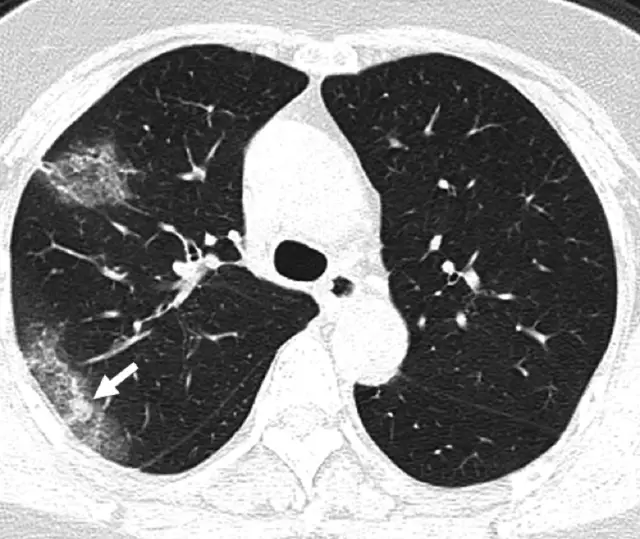

Now let's consider the CT scan of a patient who's suffering from pneumonia brought on by COVID-19.

Generally, pneumonia causes fluid to build up in the lung, which manifests itself as opacities in the lung. The literature on application of deep learning to diagnose COVID-19 using CT scans does point to some distinct characteristic features found in lung CT scans of COVID-19 as compared to other types of pneumonia, resulting from different causes.

A paper, titled Deep Learning System to Screen Coronavirus Disease 2019 Pneumonia, lists three such characteristics:

"...ground-glass appearance, striking peripheral distribution along with the pleura, and usually more than one independent focus of infections for one case."

- The first means that the opacities in the lung look like ground-glass.

- The second means that the majority of these opacities occur along the edge of the lung.

- The third means that we can have more than one such cluster of opacities.

All three of these characteristics can be observed in the CT scan image of the lung above.